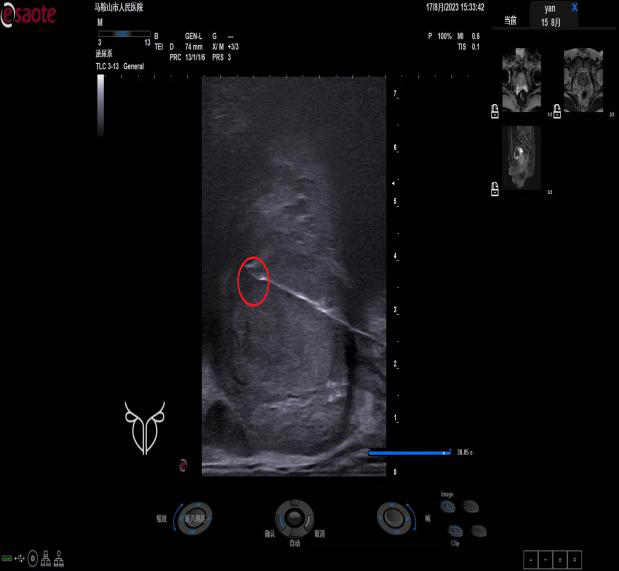

融合導航術中超聲圖像

超聲-磁共振融合導航技術的原理是利用磁共振對于前列腺診斷的高度敏感性和特異性,經(jīng)過軟件融合超聲實時引導準確定位,在病灶部位豎起“靶子”,特別是對于一些較“刁鉆”的位置,極大地提高了穿刺精確度與穿刺檢出率。與傳統(tǒng)穿刺相比,具有精準、安全、檢出率高、不需術前腸道準備、穿刺針數(shù)少(傳統(tǒng)穿刺需要穿刺8-13針)等優(yōu)勢。該項新技術的開展有助于前列腺癌的早診斷、早治療,減少穿刺相關的并發(fā)癥,提高根治率和患者的生存率。

患者楊先生因前列腺特異性抗原(PSA/TPSA)升高伴前列腺體積增大等癥狀就診。入院后,泌尿外科醫(yī)師根據(jù)患者臨床癥狀和實驗室檢查,判斷需行穿刺活檢術以明確診斷,遂向超聲醫(yī)學科發(fā)出穿刺申請,并完善了穿刺術前各項檢查檢驗。超聲醫(yī)學科介入團隊接到穿刺申請后,對患者做出全面評估,與影像科聯(lián)絡,調取磁共振影像,為患者制定了超聲-磁共振融合導航下經(jīng)會陰穿刺的診斷方案。在科副主任兼介入組長劉丹丹的指導下,超聲介入科、影像科醫(yī)生為患者精確開展超聲-磁共振融合導航下經(jīng)會陰前列腺穿刺活檢術。術中在嚴密觀測患者各項生命體征下,醫(yī)生團隊精準進行靶區(qū)穿刺,術畢給予止血、抗感染處理,并進行及時的術后病理隨訪。